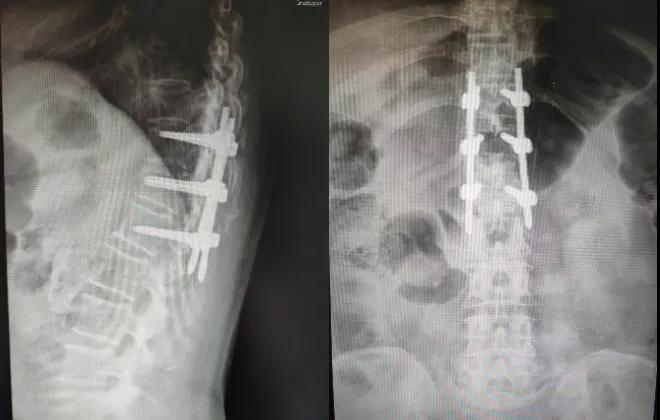

术后X片

微创经皮椎弓根螺钉经伤椎置钉固定治疗胸腰椎骨折,是相对比较完善的手术治疗方案,经过合理的应用和不断改进,能够接近传统开放手术的生物力学固定强度和复位矫形能力,同时具有创伤小,出血少,对自身脊柱的解剖结构和生物力学结构破坏较小,术后康复快,并发症少,疗效显著等优势,这一新技术的应用表明了呼和浩特市第一医院骨二科脊柱微创技术取得了新的突破和发展。